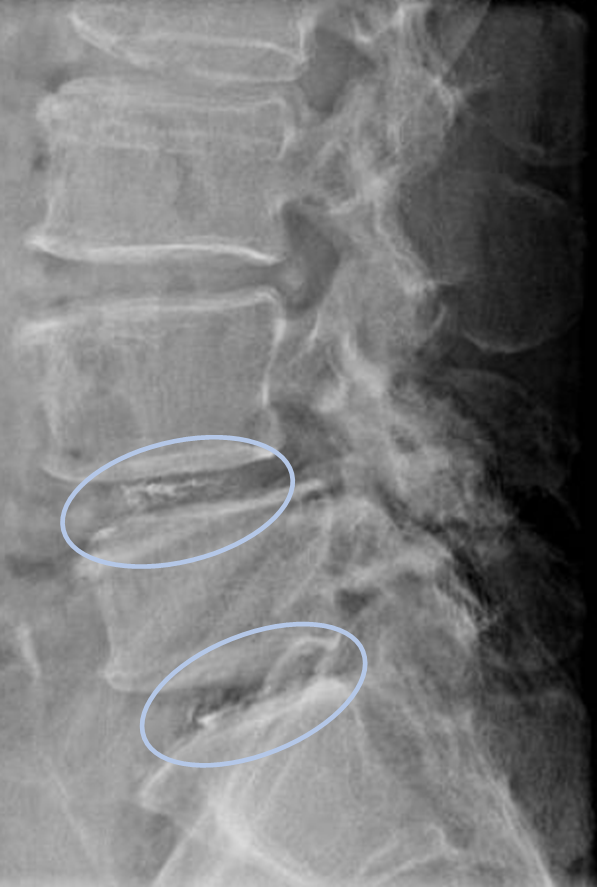

画像及び所見について

- L2/3,3/4,4/5,5/s-椎間板変性

- L4-前方すべり

以上の事が画像上認められます。

・L4/5,5/s-椎間板変性による椎間孔狭窄を認め、主症状の原因と考えられる。